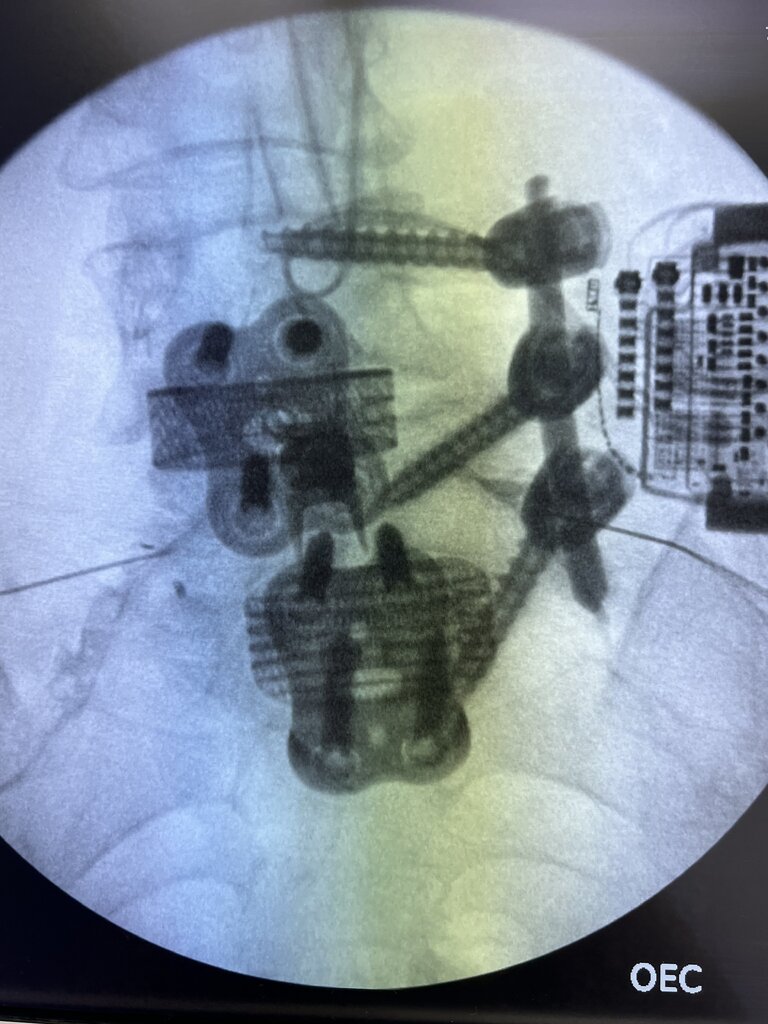

I looked at her X-ray and thought it would be ok but forgot about the IPG getting in the way on oblique. SCS from me, vertiflex and fusion from the neurosurgeon.

From yesterday.

good job, looks real challenging.

i usually offer bilateral S1 TFESI in this situation. i might try more caudals.